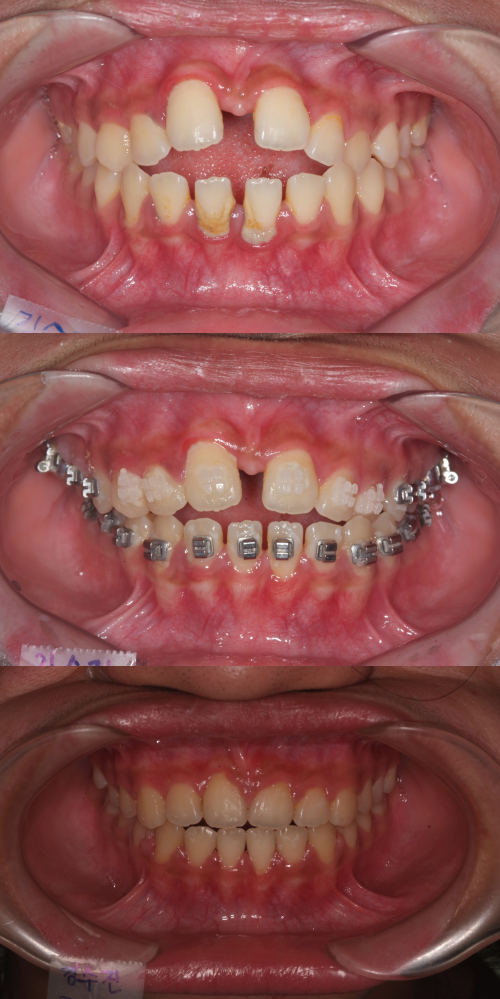

위부터 차례로 개방교합 상태, MSE 시술 후 앞니가 닫히기 시작한 단계, 한 달 반 뒤 교정된 모습. 최종석치과의원 제공 위부터 차례로 개방교합 상태, MSE 시술 후 앞니가 닫히기 시작한 단계, 한 달 반 뒤 교정된 모습. 최종석치과의원 제공

상담을 통해 위턱이 좁거나 성장이 덜 됐는지, 코로 호흡을 잘할 수 있는지 등을 살펴본 뒤 MARPE 시술 여부를 결정한다. 시술 후 한 달 정도면 입천장 확장 효과와 성공 여부를 확인할 수 있다. 혀를 내밀지 않도록 습관을 개선한다면 짧게는 한 달에서 한 달 반 정도 만에 개방교합이 뚜렷하게 교정되기도 한다. 최소 6개월 이상 장치를 유지하는 것이 좋고, 가능하다면 치아를 이동시키는 단계에도 이 장치를 사용한다.